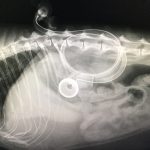

胃チューブのX線による確認